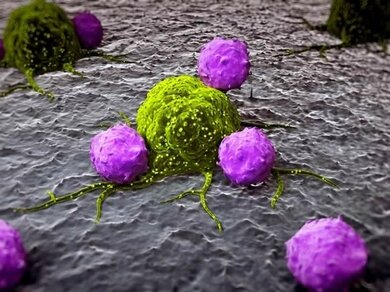

Die körpereigenen weißen Blutkörperchen greifen eine Krebszelle (grün) an

© Fotolia/Juan Gärtner

Krebs entsteht auf dem Boden genetisch veränderter Zellen, welche sich ungebremst teilen und vermehren. Im Körper gibt es viele solcher Zellen, welche aber normalerweise durch eine körpereigene Abwehr ständig zerstört werden. Gelingt es den Krebszellen sich diesem Kontrollmechanismus zu entziehen können sich Geschwulste (Tumore) bilden. Bei Krebs in der Leber handelt es sich um einen bösartigen Tumor, der von den Leberzellen ausgeht, seltener von den Gallengängen (Cholangio-Karzinom). Letztere machen ähnliche Beschwerden, werden aber anders behandelt.